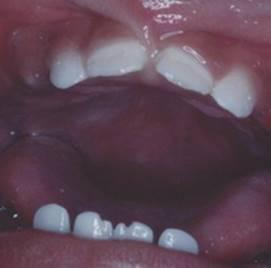

Местная гипоплазия – аплазия эмали

21 зуба (зуб Турнера)

Проявляется местная гипоплазия в виде беловато-желтоватых пятен, углублений, располагающихся на всех поверхностях. В тяжёлыхслучаях может быть аплазия (отсутствие) эмали.

Местная гипоплазия чаше наблюдается на постоянных малых коренных зубах, зачатки которых располагаются между корнями молочных зубов.

Данная патология формируется вследствие нарушения деятельности клеток, строящих эмаль, однако причины этого нарушения не связаны с минеральным обменом в организме - местная гипоплазия эмали возникает в результате механической, травмы зачатка постоянного зуба либо воспалительный процесс в нём под влиянием биогенных аминов и инфекций, поступающих в фолликул при хроническом периодонтите молочного зуба. На временных зубах местная гипоплазия не наблюдается.

Более часто причиной местной гипоплазии является воспалительный процесс, распространяющийся из области верхушки корня временного зуба или из остеомиелитического очага челюсти. Зачаток любого постоянного зуба может оказаться вовлеченным в воспалительный процесс, но чаще страдают именно зачатки премоляров, располагающихся между корнями временных моляров. Как известно, временные моляры наиболее часто поражаются кариесом, а следовательно, и верхушечным периодонтитом.